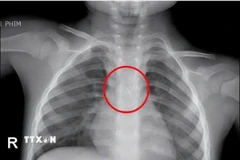

Ngày 10/5, Sở Lao động - Thương binh và xã hội tỉnh Phú Yên phối hợp với Sở Y tế và Bệnh viện tim Tâm Đức (Thành phố Hồ Chí Minh) tổ chức khám sàng lọc bệnh tim cho 500 trẻ em bị bệnh tim bẩm sinh.

Đối tượng được khám sàng lọc miễn phí là trẻ dưới 16 tuổi ở 9 huyện, thị xã và thành phố trong tỉnh, có hoàn cảnh đặc biệt khó khăn, không có điều kiện để chữa bệnh.

Theo ông Nguyễn Văn Trắc, Phó Trưởng phòng Chăm sóc - Bảo vệ trẻ em và bình đẳng giới (Sở Lao động - Thương binh và Xã hội), lần này sẽ khám sàng lọc cho 500 cháu, qua đó các bác sỹ sẽ sàng lọc và chỉ định mổ cho khoảng 50 cháu.

Toàn bộ kinh phí khám sàng lọc, mổ tim miễn phí được thực hiện theo Quyết định 55a về chính sách hỗ trợ phẫu thuật tim cho trẻ em bị bệnh tim bẩm sinh của Thủ tướng Chính phủ; Tổ chức phi Chính phủ Children (Thụy Sỹ) hỗ trợ 20 ca phẫu thuật, trung bình mỗi ca trị giá 50 triệu đồng.